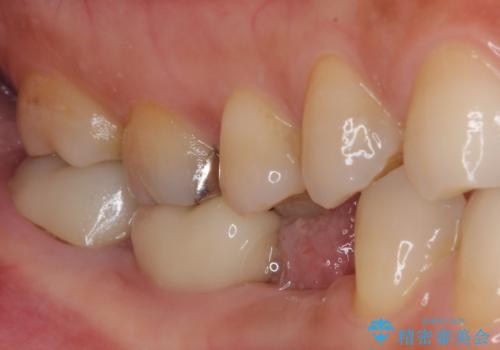

割れてしまった奥歯 インプラント治療

- 近医にて抜歯が必要と診断されたとのことで来院された患者様です。

術前の診査では、歯が破折している可能性が高いものの、確実に抜歯が必要と診断ができない状態でした。

状況次第では抜歯が必要となり、その際にはインプラント治療を行うことを了承いただいた上で、破折していない場合には根管治療を行うこととしました。

土台の材料を外して顕微鏡下で確認したところ、歯根にまで及ぶ破折が認められたため、インプラント治療を行うこととしました。

他にも銀歯や欠損となっている歯に対しての治療も希望されたため、補綴治療を行うこととしました。